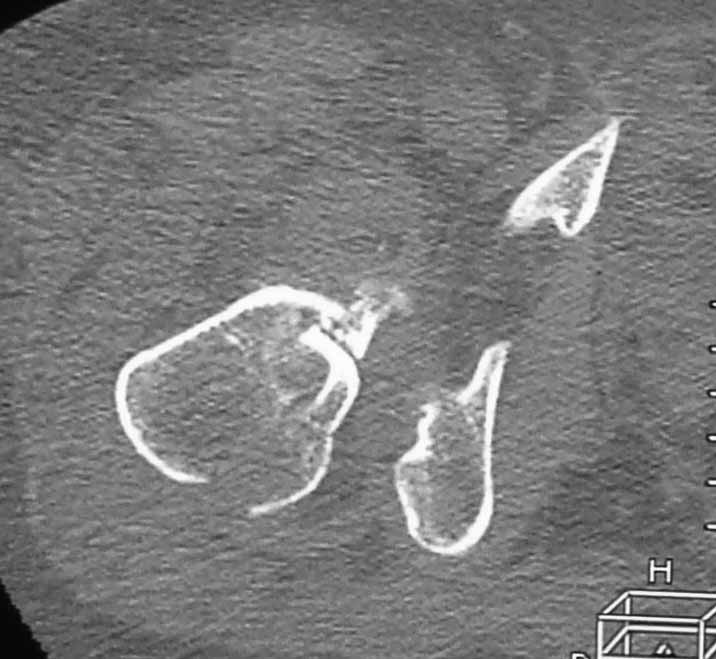

Пациентка 53 лет. ДТП 09.01.12: сочетанная травма: перелом 2-5 ребер справа, ушиб легких;

перелом обеих лонных костей без смещения; закрытый перелом проксимального конца правой

бедренной кости; открытый оскольчатый внутрисуставной перелом проксимальных концов

костей правой голени.

Бедро одномоментно делать не стал, не было уверенности в наличии перелома на уровне шейки. Во время операции смотрел тазобедренный сустав под ЭОПом,

головка неподвижна. После операции повторили КТ, стало очевидно, что имеется субкапитальный перелом. Что делать, остесинтез или протезирование? Если остеосинтез, то чем? Заранее благодарен за советы.